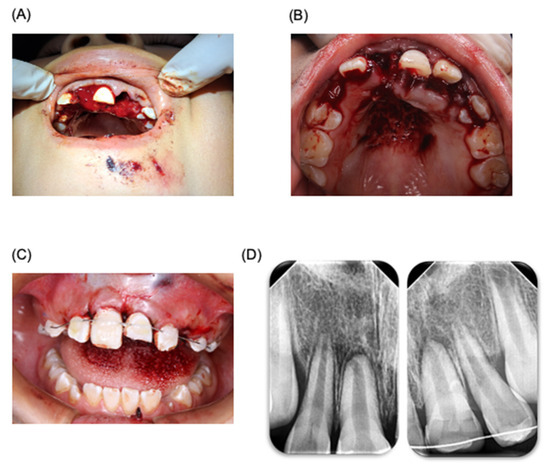

Figure 4.

Oral rehabilitation. Treatment of oral rehabilitation of patient. (A) Restauration protocol carried out. (B) Clinical revision at 7 months after accident. (C) Placement of the personalized sports guard. (D) Space maintainers placed in the patient’s mouth.

Three months later, the patient was referred to a specialist in esthetics, cosmetics, restorative, and implant dentistry (clinic of prothesis, specializing in esthetics, cosmetics, and restorative and implant dentistry, Faculty of Dentistry, Autonomous University of San Luis Potosi, SLP, Mexico). A direct resin restoration for tooth 21 was performed using a guide and stratification technique with prior waxing (Figure 4). Two weeks later, the patient visited the pediatric dentistry clinic for the placement of a custom sports guard, with follow-up appointments scheduled weekly. A month later, prophylaxis treatment and topical fluoride application were administered. In the subsequent months, a lingual arch and a Nance button were installed to maintain space, with ongoing control appointments. After a month and a half, both the lingual arch and the Nance button were removed (Figure 4), Currently, nine months post accident, the patient continues to be monitored by both pediatric dentists and endodontics, and is currently showing a positive prognosis; however, it will be necessary to evaluate at patient for long time in order be sure of success in treatment.